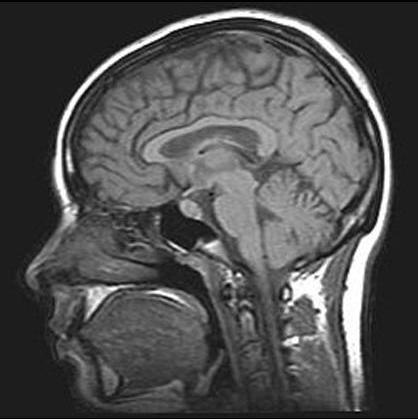

محققان رایانه در الکنور دیموس (Elecnor Deimos) اسپانیا پس از سالها تجربه در زمینه تجزیه و تحلیل عکسهای ماهوارهای، برنامهای ساختهاند به نام AlzTools 3D Slicer که در تحلیل تصاویر رزونانس مغناطیسی (MRI) بکار میرود، و مسیرهای فضایی را با تجزیه و تحلیل اسکن مغز انسان سازگار میکند.

با استفاده از آلزایمرتولز (AlzTools)، دانشمندان دیموس با داده های خام بدست آمده از اسکن مغز، به جای تصاویر ماهواره ای کار کرده و به جای مشاهده یک میدان یا یک مسیر در تصویر ماهواره ای، آنان مناطقی از مغز مانند هیپوکامپ را بررسی میکنند، که در ارتباط با آلزایمر است.